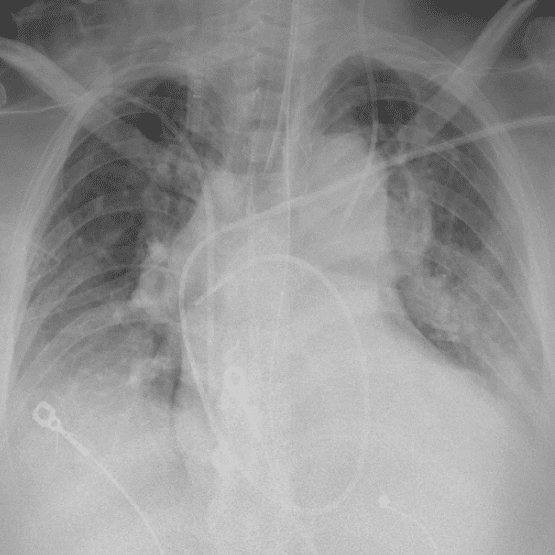

Practice Cases